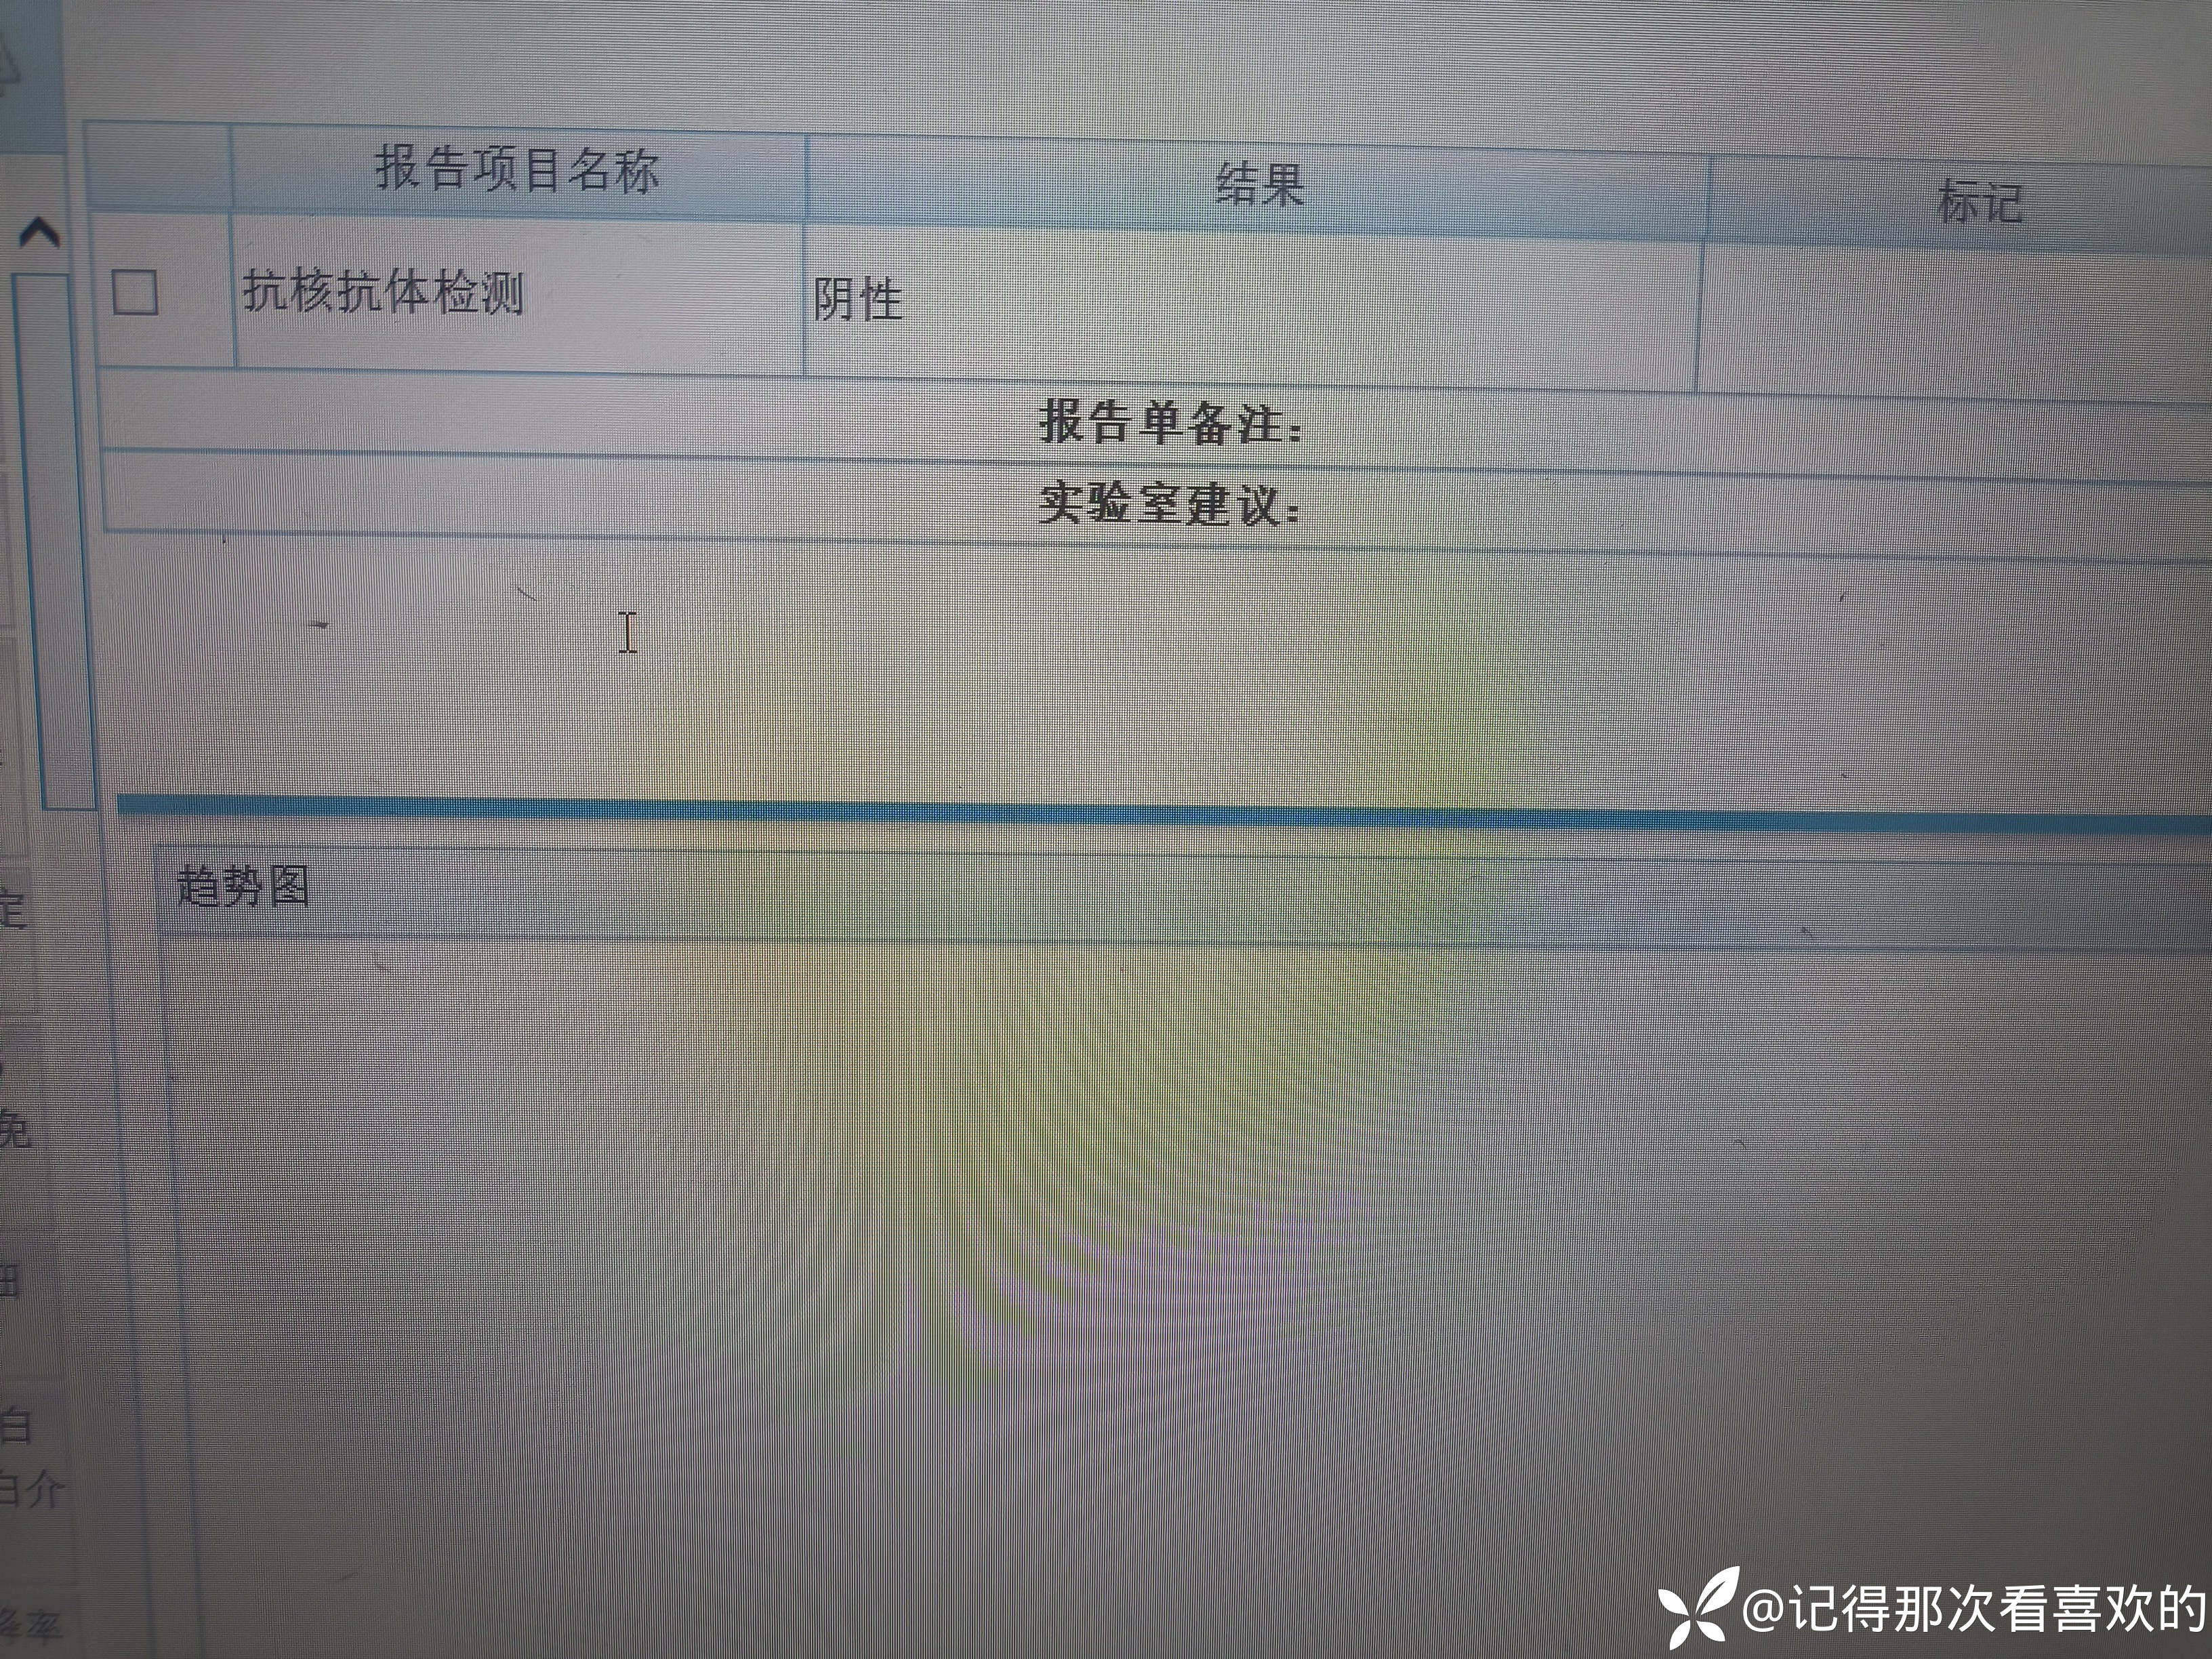

病例特点:患者钟某 男,14岁,以"髋、膝、足肿痛1年余,加重3日。"为主诉入院。现病史:缘于1年前无明显诱因出现左侧髋关节、双足跟、左踝关节、右足第一足趾关节肿胀、疼痛, 疼痛呈持续性,多于阴雨天、活动后症状加重,疼痛未向他处放射、转移,症状严重时行走困难。遂就诊于我科,查"HLA-B27(+)、CRP 70mg/L、骶髂MR:骶髂关节肿胀",诊断为"强直性脊柱炎",先后予皮下注射"司库其尤单抗150mg qw、阿达木单抗40mg q2w",上述症状较前好转,此后不规律用药,于半年前自行停用上述药物,未再规律随诊。3日前再发左膝、双肘关节肿痛,性质同前,程度较前加重,影响行走,伴有发热,体温最高达39℃,自行服用退烧药(具体不详)后体温较前下降,上述关节肿痛无明显改善。现为求进一步治疗,就诊我院,门诊拟"强直性脊柱炎"收住入院。体格检查:T36.6℃ P138次/分 R50次/分BP/120/68mmHg 专科情况:生命征平稳,神志清楚,双肺呼吸音清,未闻及干湿啰音,心律齐,各瓣膜听诊区未闻及杂音,全腹软,无压痛及反跳痛,未触及包块,双肘、左膝关节肿胀、压痛、触之皮温高。双下肢无浮肿,病理征未引出。

诊疗计划:1.入院予二级护理,监测血压、脉搏、呼吸。2.入院完善三大常规、凝血、生化、骶髂MR、彩超、CT、心电图等相关检查评估病情。3.治疗上暂予抗炎镇痛,辅以护胃治疗,待相关检查结果回报后进一步治疗,本次就诊拟行生物制剂治疗,予完善骨保护药物,传染病相关检查排除禁忌症,患者本次发病伴有发热达39℃,追问病史患者诉偶有干咳不适,目前已改善,予完善呼吸道病原学检查明确病情。4.患者Padua评分1分,属于发生VTE低危风险,实行VTE基本预防,动态评估Padua评分。5.已将目前病情及现有临床诊断以及存在疾病复杂性、个体的差异性、对治疗的反应不同、鉴于目前医学技术水平有限,和下一步相关诊疗详细充分告知患者家属,取得家属的理解并同意配合下一步诊疗及检查。6.NRS-2002评分3分,目前患者营养状态尚可,进食情况尚可,根据病情变化动态评估。